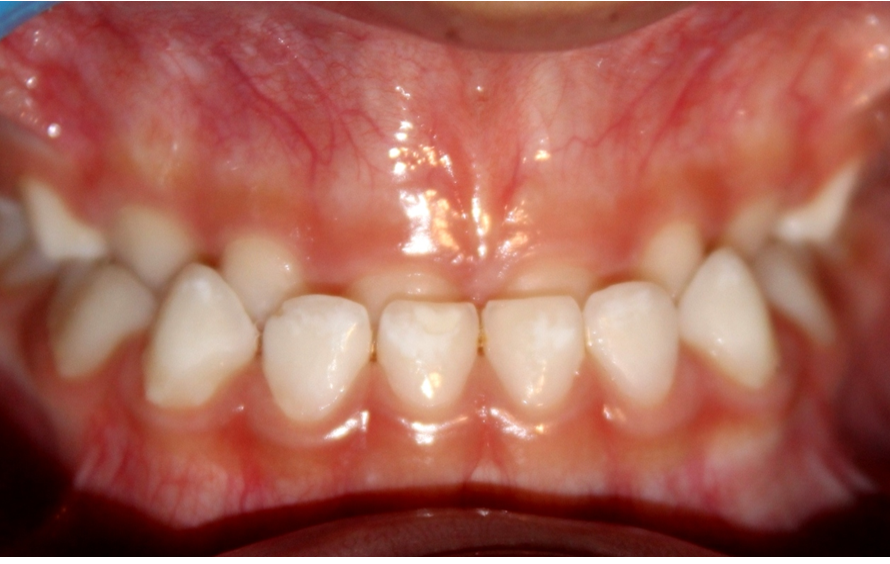

Mordida cruzada posterior bilateral